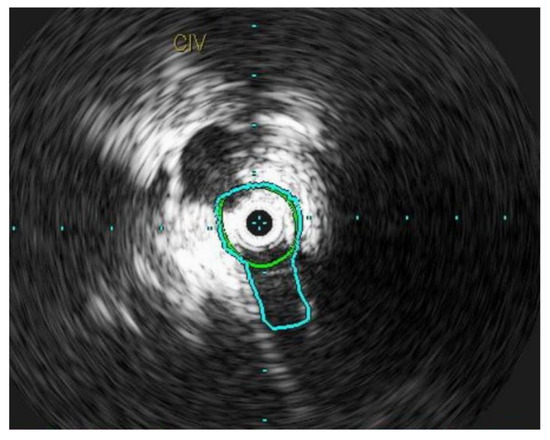

Chronic compression can lead to inflammation within the lumen of the vein, resulting in intimal fibrosis [48]. This ultimately leads to a localized flow disturbance and peripheral venous hypertension (Figure 4). The mean age of presentation is 42.6 ± 16.9 years [49]. However, contrary to the traditional description, iliac vein compression syndrome can occur in both genders, on both sides, and at any age [47]. Several other anatomical variants have been reported in literature and all of these lesions are known as NIVLs [50].

Figure 4.

L common iliac vein is compressed between the vertebral body and the artery and appears as a narrow slit like structure.